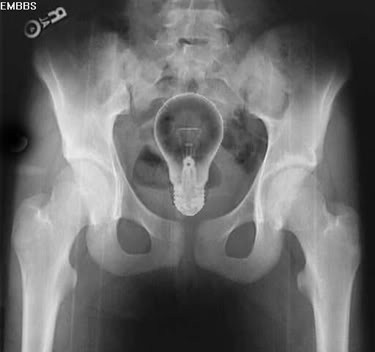

Одним из лидеров недели в Twitter стал хештег #WeirdThingsToPutUpYourAss (Странные штуки, которые суют в задницу). Проктологи со всего мира поделились рентгеновскими снимками содержимого анусов своих пациентов. Выяснилось, что огурец - еще не самое удивительно, что можно обнаружить там, где не светит солнце.